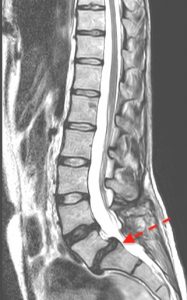

Cuando van asociadas a “desgaste” (crecimiento de hueso en las articulares posteriores) sin fractura de pars, se suelen denominar degenerativas y aparecen en L4-L5.

Muchas de ellas son estables y no requieren tratamiento quirúrgico de por sí. Otras, en cambio, van asociadas a estenosis de canal (provocada también por el mismo “desgaste” en los discos, en la protrusión de ligamentos sobre el canal o en la inflamación de las articulares) y suelen cursar con clínica de estenosis de canal lumbar degenerativa.

Algunas veces es necesario asociar instrumentación (tornillos) bien porque existen signos de inestabilidad previa o porque la propia cirugía puede afectar los elementos de contención.